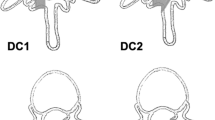

Each specimen was tested in the native state and after surgery. In the T13–L5 specimens, surgery was performed on the L2–L3 IVD. Via a left lateral approach, a small, transverse stab incision was made into the middle of the IVD with a #11 surgical blade. All NP material was removed (nucleotomy) through the annular incision, using a ball-tipped probe and grasping forceps. The L1–L2 IVD was left intact and served as a control. In the L5–Cd1 specimens, surgery was performed on the lumbosacral (L7–S1) junction via a dorsal approach. The dorsal vertebral arch was removed [dorsal laminectomy; Fig. 1a)] as described previously [13], leaving the articular facets intact. Subsequently, nucleotomy of the L7–S1 IVD was performed as described for the L2–L3 IVD, but through a dorsal annular incision (Fig. 1b). The L6–L7 IVD was left intact and served as a control. The structural composition of all surgically removed NPs was examined macroscopically. The NP taken from the NCD discs was gel-like, similar to the NP seen in Thompson grade I IVDs, whereas the NP from the CD discs had a fibrocartilaginous appearance, similar to the NP seen in Thompson grade II IVDs (Fig. 2) [14].